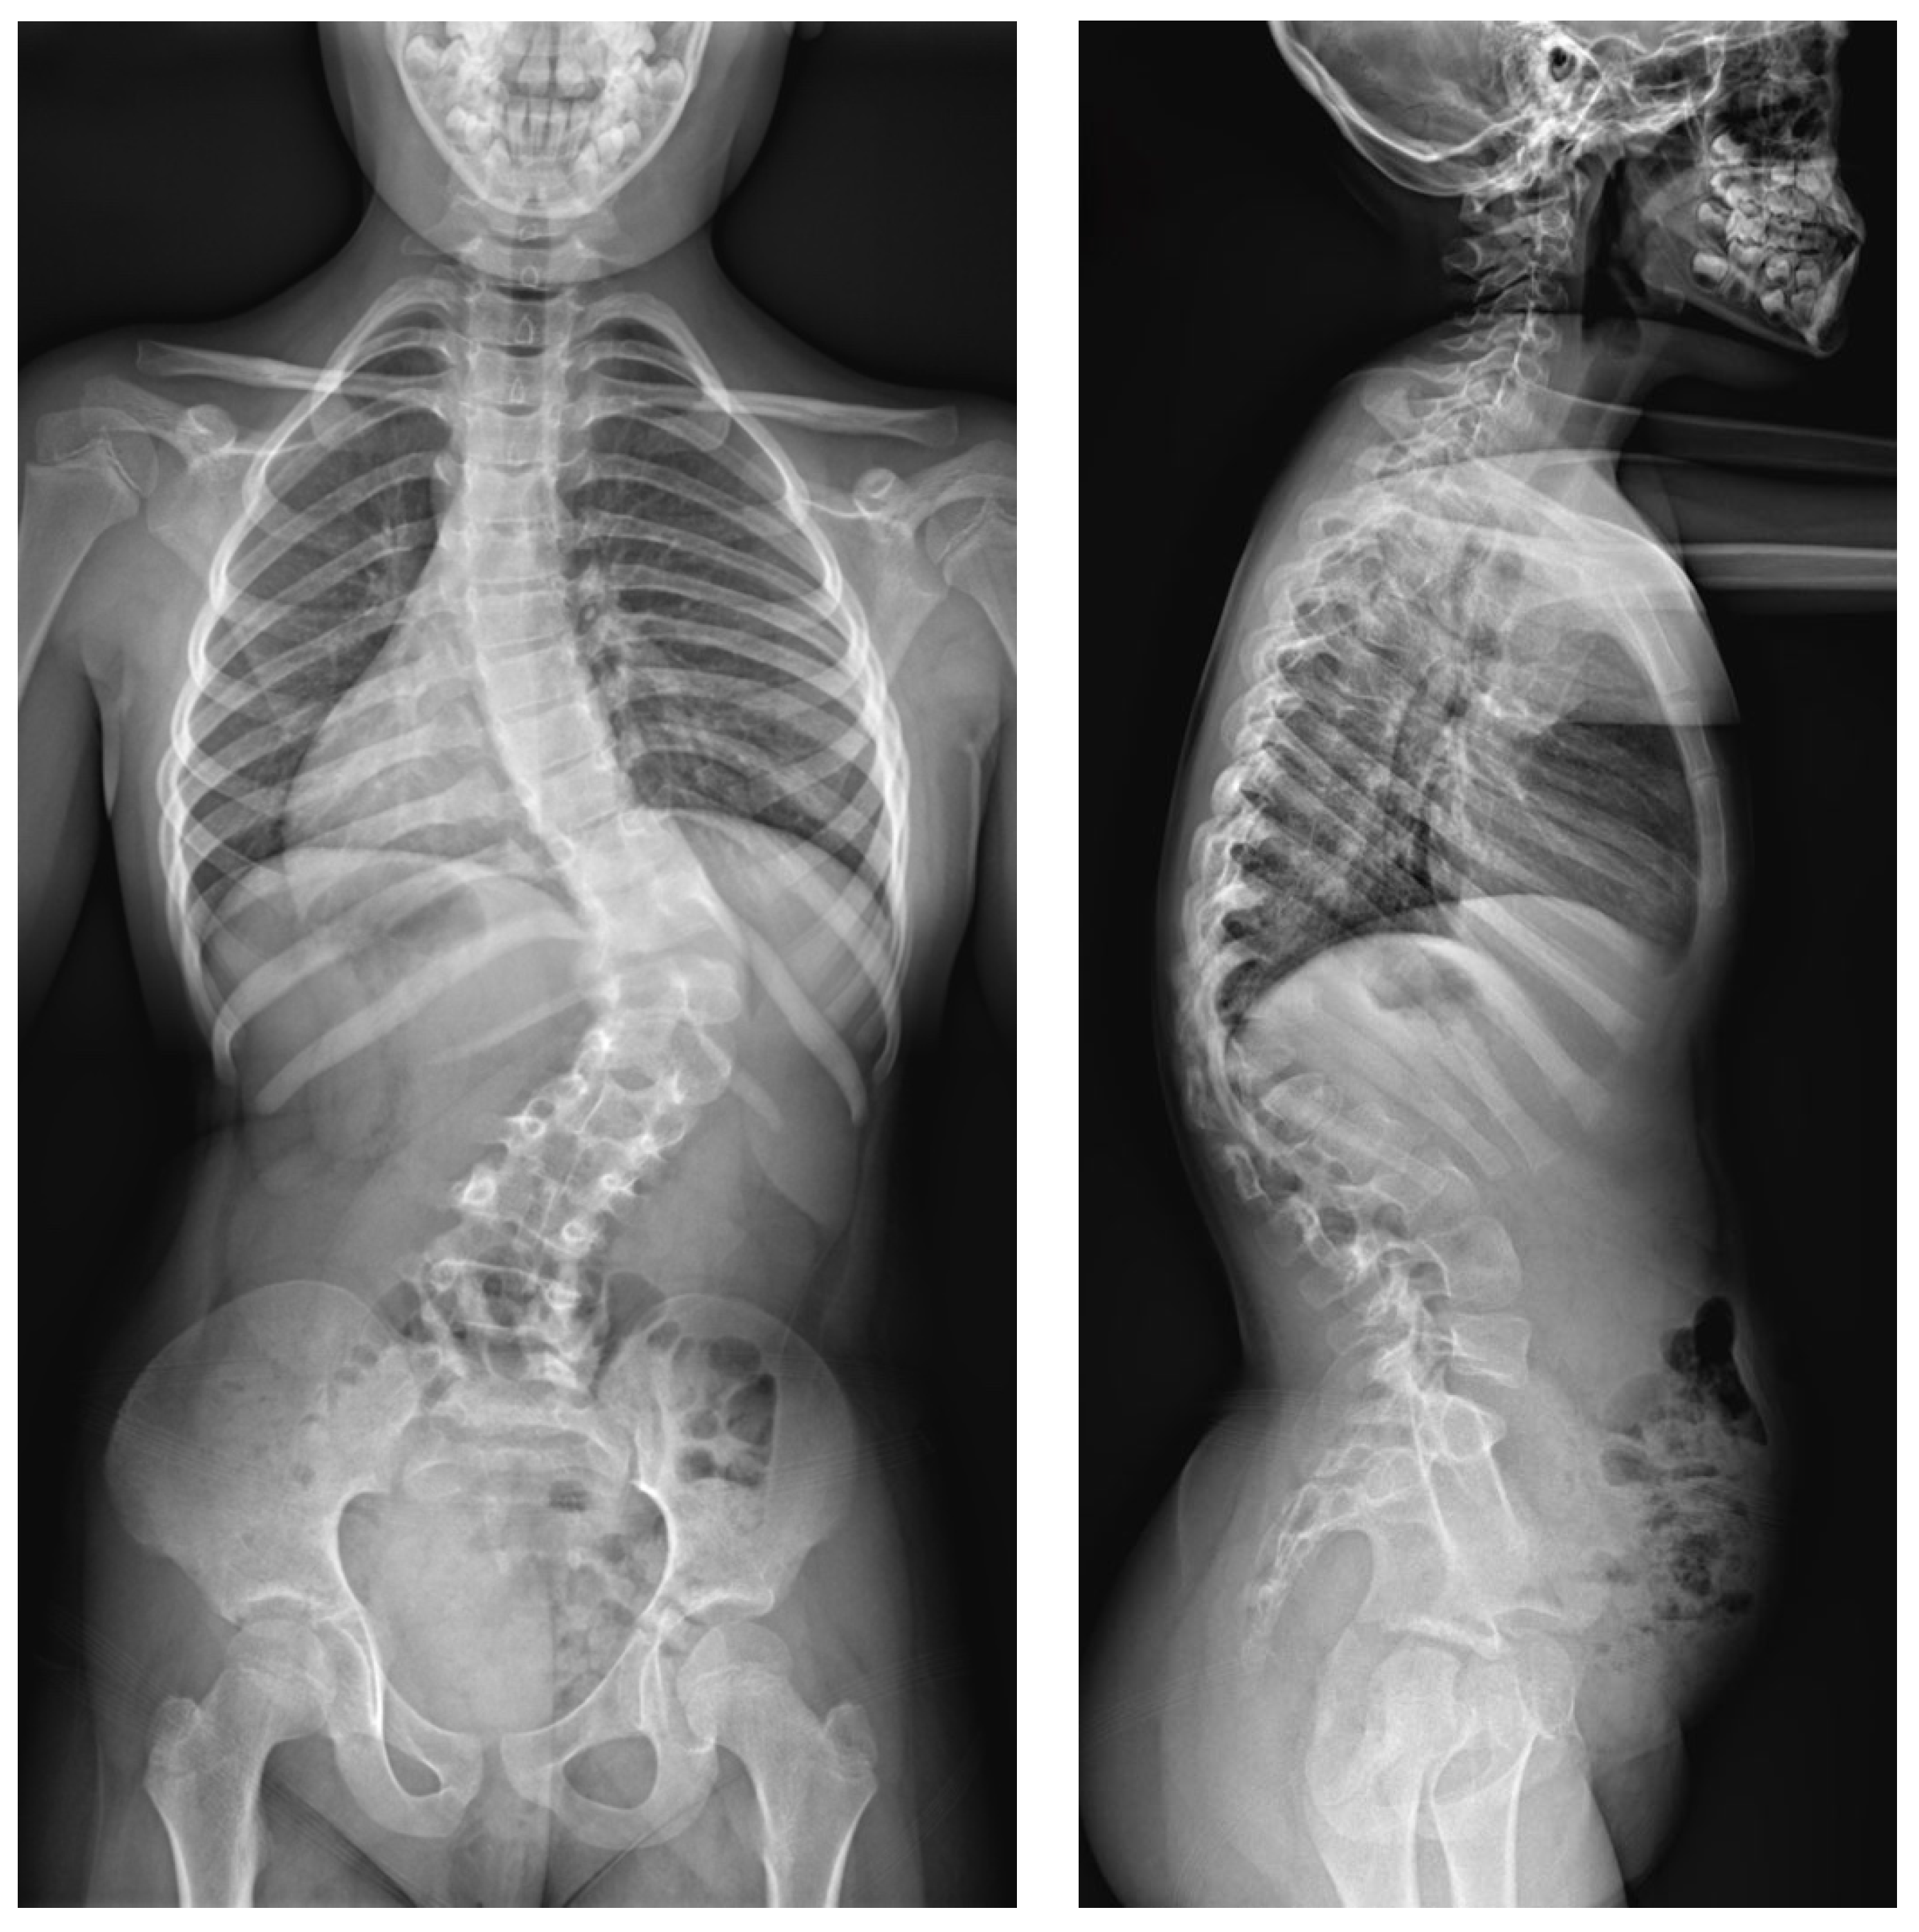

2.2. Example of Early-Onset Idiopathic Scoliosis